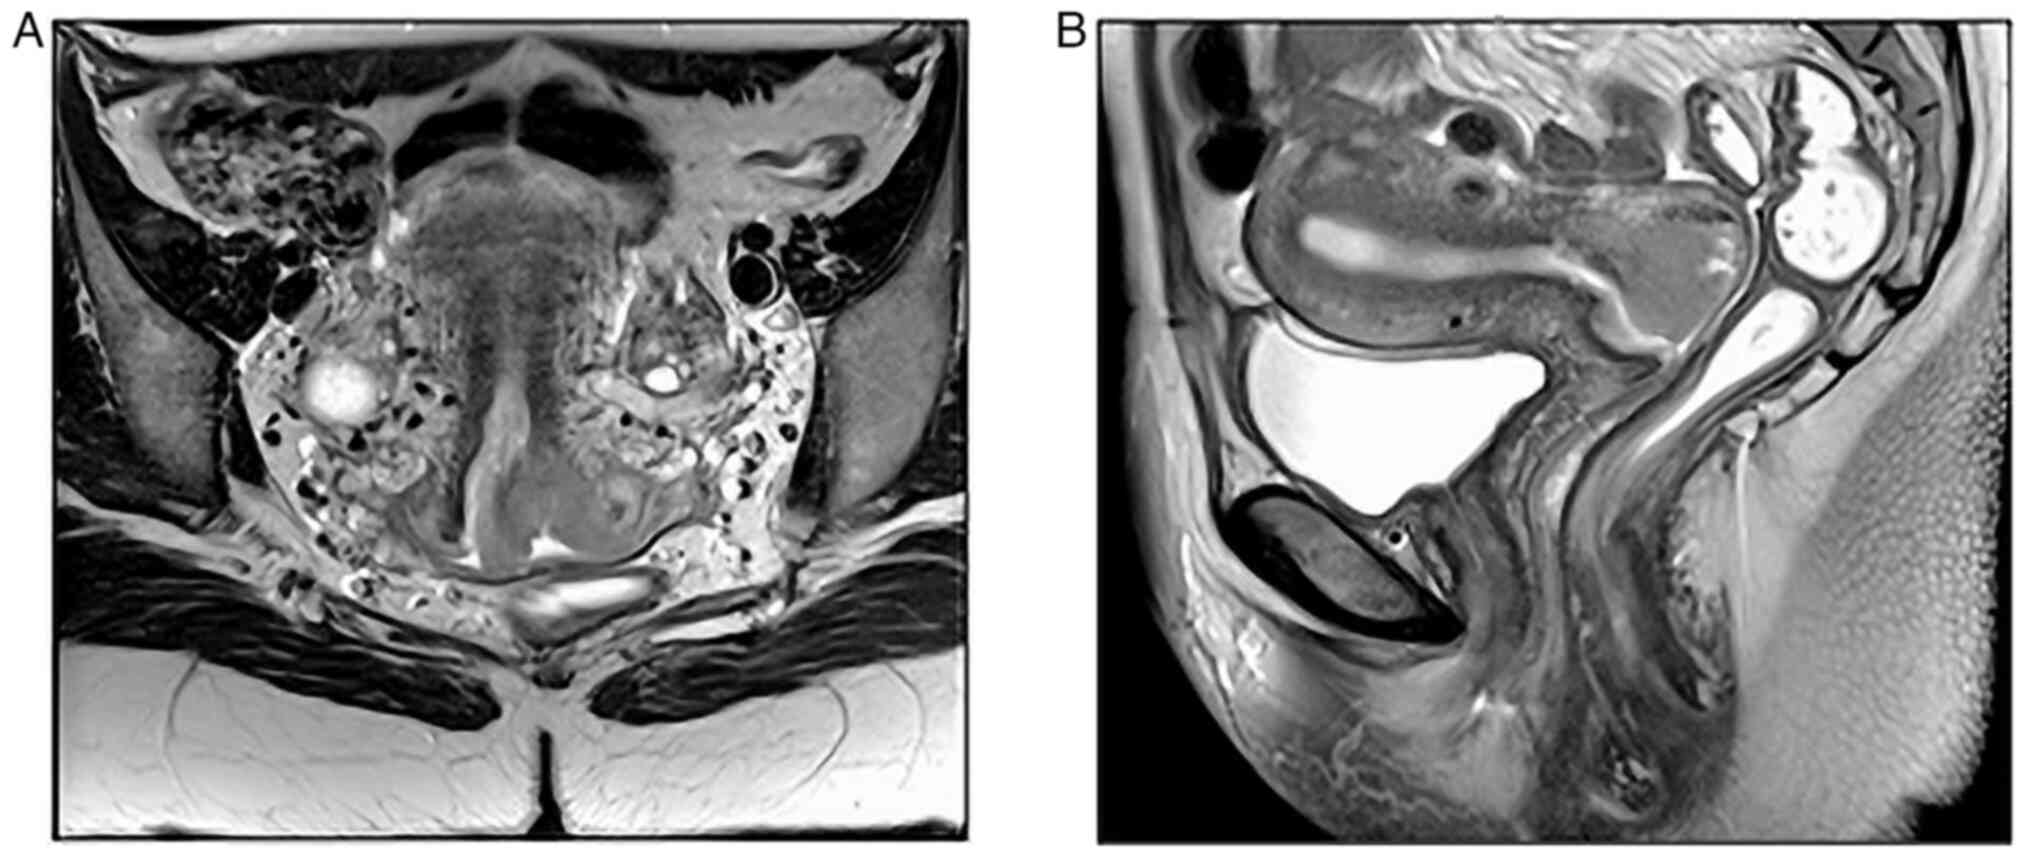

Magnetic resonance showed intimal contact of the mass with the vaginal posterior wall and suspicion of parametrial affection. Furthermore, an enlarged lymph node was found in the left external iliac region, with no evidence of retroperitoneal lymphadenopathies (Fig. 1).

Figure 1

Magnetic resonance imaging. (A) Coronal section: Mass occupying uterine cervix. (B) Sagittal section: Mass in intimal contact with the vaginal posterior wall.